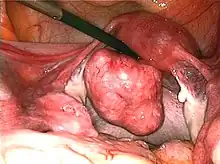

| Uterine fibroids as seen during laparoscopic surgery | |

- A laparoscopic myomectomy is done through a small incision near the navel. The physician uses a laparoscope and surgical instruments to remove the fibroids. Studies have suggested that laparoscopic myomectomy leads to lower morbidity rates and faster recovery than does laparotomic myomectomy.[54]

Submucosal fibroid in hysteroscopy Treatment of an intramural fibroid by laparoscopic surgery

Treatment of an intramural fibroid by laparoscopic surgery After treatment of an intramural fibroid by laparoscopic surgery

After treatment of an intramural fibroid by laparoscopic surgery